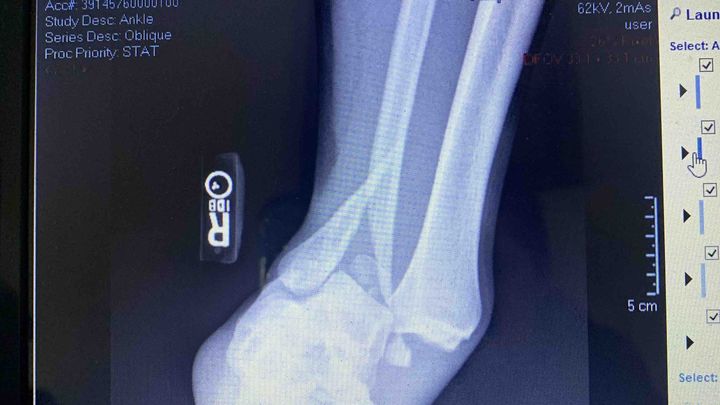

We are raising money to help with Nate’s surgery. He shattered his ankle in three different places and is in horrible amounts of pain. Anything helps.